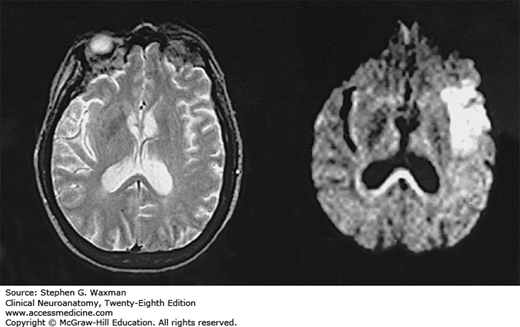

Cerebral infarct shown by diffusion-weighted imaging (DWI). On the left, a conventional MRI (T2-weighted image) 3 hours after stroke onset shows no lesions. On the right, DWI 3 hours after stroke onset shows extensive hyperintensity indicative of acute ischemic injury. (Reproduced, with permission, from Warach S, et al: Acute human stroke studied by whole brain echo planar diffusion weighted MRI. Ann Neurol 1995;37:231.)